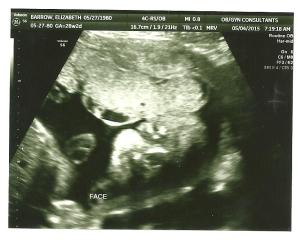

If you look closely, you will see a smooshed baby face turned sideways and two little fists below the face….hello baby Luke!

Best moment this week: The ultrasound, of course. I seriously was stressing about it because we had a red flag on our last ultrasound, but everything was measuring great. He is 2 pounds 11 ounces right now and dead on for all of the other stats! Phew. I thought that the stress of the Chicago trip would have caused something!

(Another face shot. Sideways. Ultrasounds are creepy.)